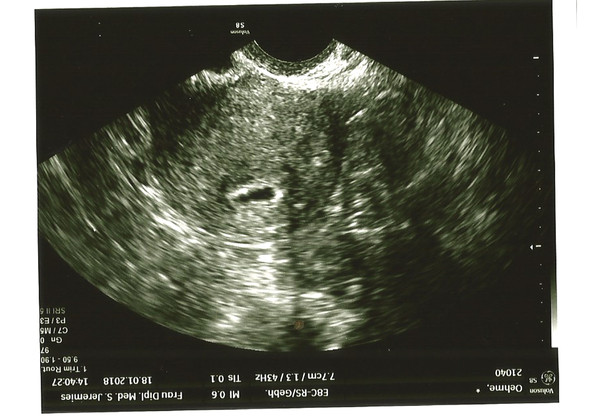

11 Schwangerschaftswoche Alles zur Größe des Babys und Entwicklung in Ihrem Bauch, Anzeichen, Gewichtszunahme und Untersuchungen wie Ultraschall. Um eine Schwangerschaft eindeutig festzustellen, wird der Frauenarzt zusätzlich zu einem Schwangerschaftstest im Rahmen der Erstuntersuchung gewöhnlich einen ersten Ultraschall durchführen Das ist etwa ab der 5 oder 6 Schwangerschaftswoche (SSW) möglich In der 6SSW ist eine Chorionhöhle von etwa zehn Millimetern Durchmesser mit einer umgebenden verdickten, unregelmäßigen. Habe dir mal das Bild von meiner Schwangerschaft bei 54 angehängt Wie du siehst, ist da auch nicht mehr zu sehen Bei 70 hatte ich den nächsten Termin und da sah man den Embryo mit schlagendem Herzchen Bin mittlerweile in der 16 Woche und dem Baby gehts gut.

So kannst du im Mutterpass auch immer den genauen Fortschritt deiner Schwangerschaft ablesen SSW 6 1, SSW 6 2 oder SSW 6 3 bedeutet nicht etwa, dass du dich in der 6 Schwangerschaftswoche befindest, sondern dass du diese vielmehr bereits beendet hast und schon in der 7 SSW bist. Das was auf dem Bild zu sehen ist, ist völlig normal!. Um eine Schwangerschaft eindeutig festzustellen, wird der Frauenarzt zusätzlich zu einem Schwangerschaftstest im Rahmen der Erstuntersuchung gewöhnlich einen ersten Ultraschall durchführen Das ist etwa ab der 5 oder 6 Schwangerschaftswoche (SSW) möglich In der 6SSW ist eine Chorionhöhle von etwa zehn Millimetern Durchmesser mit einer umgebenden verdickten, unregelmäßigen.

Antwort Eine Schwangerschaft kann dann sicher nachgewiesen werden, wenn in der Gebärmutter eine Fruchthöhle mit einen Embryo oder einer Struktur, die zu der Fruchtanlage gehört (Dottersack), zu sehen ist Das ist mit guten UltraschallGeräten etwa ab der 5 bis 6 Schwangerschaftswoche möglich, also ab einer Woche nach Ausbleiben der Regel. Ein sicherer Nachweis der Schwangerschaft über Ultraschall ist aber erst ab der sechsten Schwangerschaftswoche möglich Trotzdem ist auch jetzt schon etwas im Ultraschall zu auszumachen Der Embryo sieht auf dem Bild wie ein Punkt aus, der etwa die Größe eines Stecknadelkopfs hat 6 Woche 4 Woche Zurück zur Übersicht Diese Artikel. Was bedeutet 6 SSW?.

Eine Woche später ist der Dottersack zu sehen Die Fruchthöhle ist jetzt ca 10 mm groß Bild 2 Wenn die Fruchthöhle 1 cm groß ist oder man sicher sein kann, dass die 6 SSW begonnen hat, sollte der Dottersack (roter Pfeil) zu sehen sein Es sind wieder nur einige e und das Kind erscheint im UltraschallBild. Erfahre jetzt, wie hoch der hCGWert für jeden einzelnen der Schwangerschaft sein soll Mit unserer hCGTabelle erhälst Du alle wichtigen hCGWerte für Blut und Urin Wir verraten Dir außerdem, welche Schwangerschaftstests sensitiv genug sind, um frühzeitig hCG nachweisen zu können. 11 Schwangerschaftswoche Alles zur Größe des Babys und Entwicklung in Ihrem Bauch, Anzeichen, Gewichtszunahme und Untersuchungen wie Ultraschall.